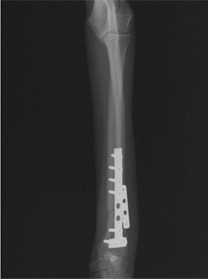

トイプードル 右遠位橈尺骨短斜骨折のALPSによる内固定

Locking Compression Plate

LCPは、スクリュー(ネジ)とプレート(金属の板)をロックする特殊な構造により骨折部位を固定する新しい世代のプレートシステムです。ひとつのホールでロッキングスクリューとスタンダードスクリューの使用を選択できるユニークな構造をしているため、骨折断端間の圧迫を目的とした従来型プレート固定法に加え、高い角度安定性を有するロッキングスクリューを用いた固定法の選択が可能です。従来のプレートシステムでは困難だった部分の骨折や癒合不全の症例に高い治療効果をもたらします。

7.1.5mmと薄いプレートのため、超小型犬にも使用しやすい